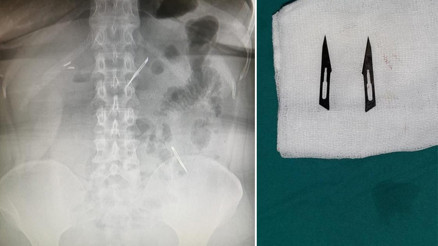

#ThodexAnkara'da karın ağrısı şikayetiyle hastaneye başvuran 46 yaşındaki kadının midesinde 2 adet neşter tespit edildi. Neşterlerin vücuduna nasıl girdiğini bilmediğini söyleyen kadın, ekmek ile birlikte yutmuş olabileceğini ifade etti. Gerçekleştirilen başarı operasyon ile neşterler vücudundan çıkarılan kadının sağlık durumunun iyi olduğu öğrenildi.

#ANKARA